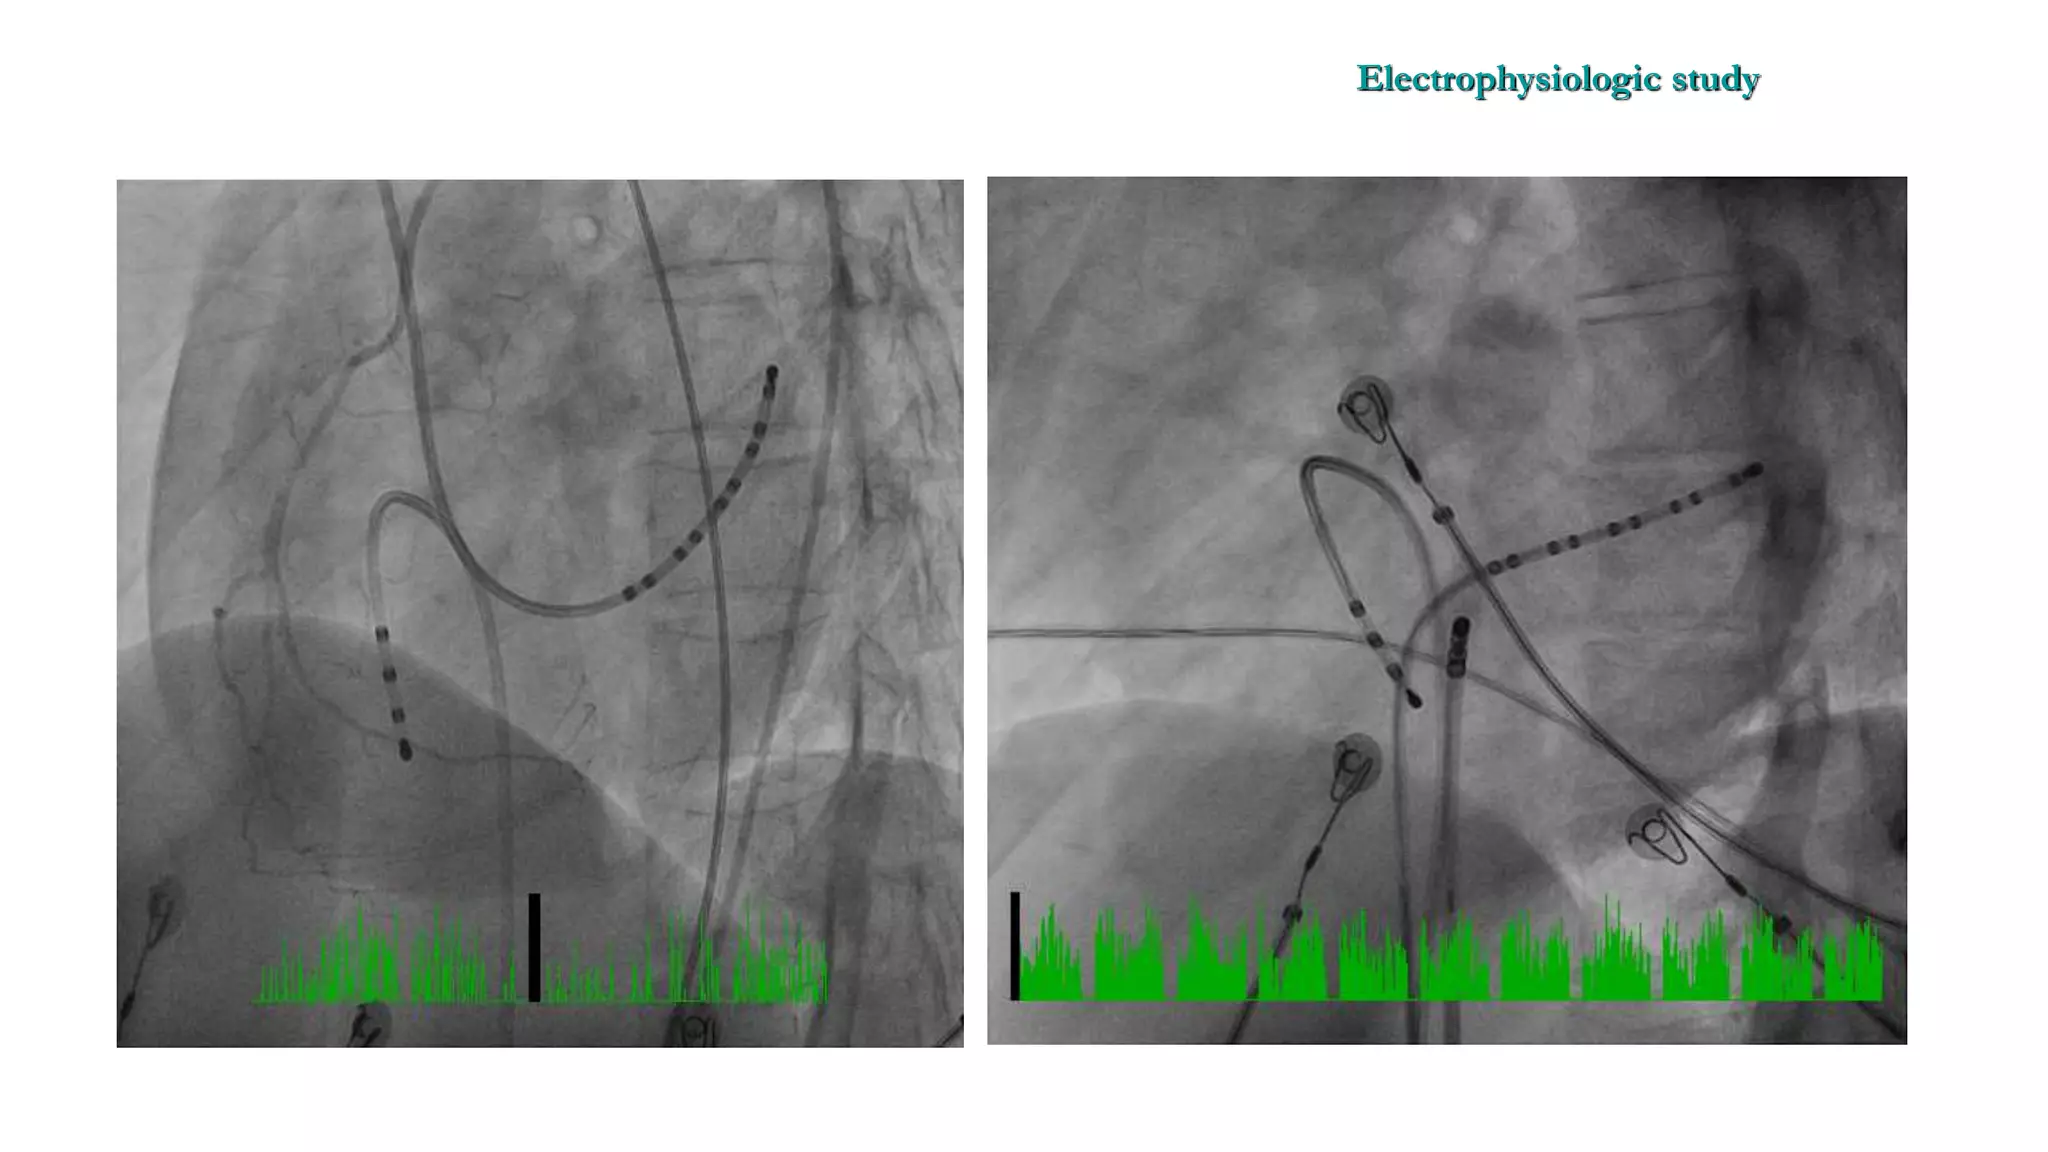

An electrophysiologic study involves inserting electrode catheters into the heart to record electrical activity and induce arrhythmias. The document discusses: 1. The procedure involves placing catheters in the heart to record electrograms from the atria, His bundle, ventricles and coronary sinus. 2. The aims are diagnostic to evaluate arrhythmias and bradycardias, and therapeutic for ablation of arrhythmias. 3. Key measurements taken include intervals between P waves, His bundle activation and QRS complex to identify conduction abnormalities. 4. Tracings are analyzed to determine the rhythm, sequence of activation, effects of pacing, and identify arrhythmia mechanisms like accessory pathways